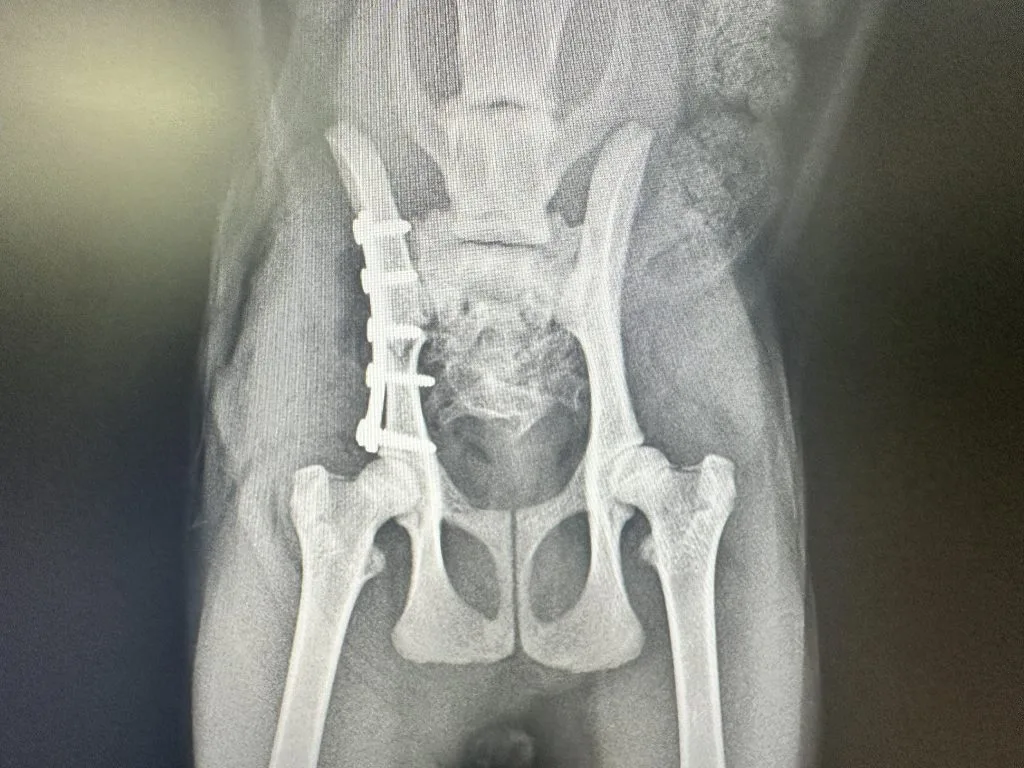

いざという時に役立つ! 犬と猫の骨折・脱臼の初期対応。裁断済み】犬と猫の骨折・脱臼の初期対応。股関節脱臼に対して大腿骨頭切除を行った症例 ~横浜みどり動物。ご覧いただきありがとうございます。裁断済みとなっておりますので、購入の際はご注意ください。「いざという時に役立つ! 犬と猫の骨折・脱臼の初期対応」定価: ¥ 15,400注意⚠️・スキャン時のスレ・ヨレ等はあるかもしれません。ScanSnapiX1600で問題なくスキャン出来ました。・裁断済みのため「全体的に状態が悪い」にしております。高額な書籍になるため、商品説明はよくご確認の上ノークレームノーリターンにてよろしくお願いいたします。。後肢の骨折・脱臼 | 「香川県高松市の総合動物病院」 すざき動物病院。増補改訂版 笠井資料/日本女性の外性器―統計学的形態論 笠井 寛司。必ず上達歯科小手術 : ここからはじめる!これならできる!テクニック。機能解剖学的触診技術 上下巻 改訂第2版。【新品・未開封・未使用】イヤーノート 内科・外科編2026。薬がみえる vol.1-4 セット

• 股関節脱臼に対して大腿骨頭切除を行った症例 ~横浜みどり動物

• 後肢の骨折・脱臼 | 「香川県高松市の総合動物病院」 すざき動物病院